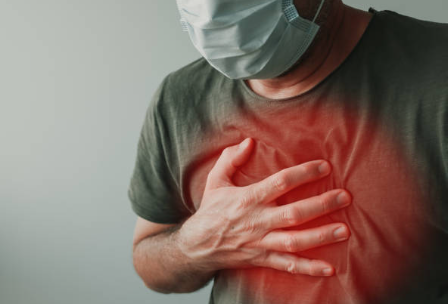

**폐기흉(肺氣胸, Pneumothorax)**은 폐 안의 공기가 새어 나와 흉강(가슴막 안쪽 공간)에 고이면서 폐가 압박을 받아 정상적으로 팽창하지 못하는 상태를 말합니다.

- 갑작스러운 가슴 통증

- 숨이 차고 호흡 곤란

- 심할 경우 기흉으로 인해 폐가 크게 눌리면서 호흡 부전 발생 가능

폐기흉은 단순히 “숨이 차다” 정도의 가벼운 증상이 아닙니다. 치료가 늦어지면 심각한 합병증으로 이어질 수 있습니다.

따라서, 중장년층은 갑작스러운 가슴 통증이나 호흡 곤란이 나타나면 지체 없이 응급실을 찾아야 합니다.